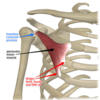

Pectoralis Minor

Action: stabilizes scapula by drawing it inferiorly and anteriorly against the thoracic wall

Sup/prox: 3rd to 5th ribs near costal cartilages

Inf/dist: medial border and superior surface of coracoid process of scapula

Innervation: Medial and lateral pectoral n. C6, C7, C8